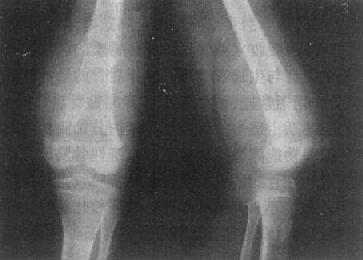

长骨巨细胞瘤的X线表现多较典型(图2-1-23),常侵犯骨端,症变直达骨性关节面下。多数为偏侧性破坏,边界清楚。瘤区X线表现可有两种类型,较多的病例破坏区内可有数量不等、比较纤细的骨嵴。X线上可见似有分隔成为大小不一的小房征,称为分房型。少数病例破坏区内无骨嵴,表现为单一的骨质破坏,称为溶骨型。病变局部骨骼常呈偏侧性膨大,骨皮质变薄,肿瘤明显膨胀时,周围只留一薄层骨性包壳。肿瘤内无钙化或骨化致密影,邻近无反应性骨膜增生。边缘亦无骨硬化带,如不并发骨折也不出现骨膜增生。破坏区骨性包壳不完整,并于周围软组织中出现肿块者表示肿瘤生长活跃。肿瘤边缘出现筛孔状和虫蚀状骨破坏,骨嵴残缺紊乱。侵犯软组织出现明确肿块者,则提示为恶性骨巨细胞瘤。肿瘤一般不穿破关节软骨,但偶可发生,甚至越过关节侵犯邻近骨骼。

桡骨巨细胞瘤桡骨骨端边界清楚的骨破坏

图2-1-23 桡骨巨细胞瘤桡骨骨端边界清楚的骨破坏,

其中有多个骨隔将骨破坏区分成多个小房,病变有膨胀性